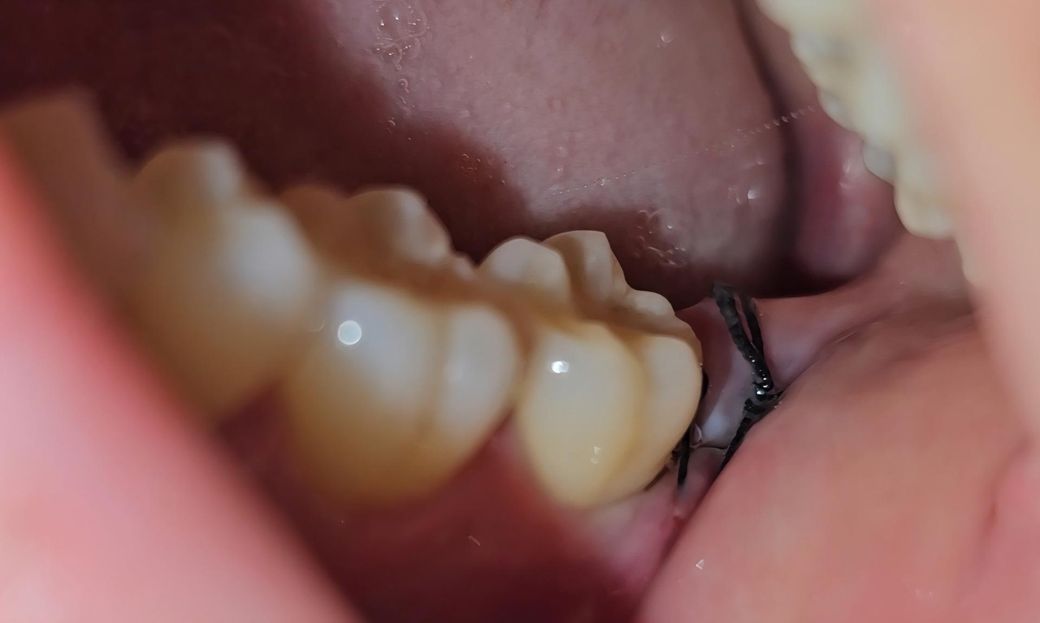

사랑니 발치 6일차인데 잘 아물고 있는 건가요?

6일차인데 아직도 입을 벌리면 불편감이 있고

발치한 부분에 칫솔이 닿으면 아픕니다ㅜ

실밥쪽에 흰색이 보이는데 저건 뭔가요?

실밥 꼬매놓은 쪽 옆(앞)에 또다른 실이 보이는데 저건 뭘까요ㅜㅜ 실밥이 2개일수도 있나요? 치아는 오른쪽 아래 사랑니 하나만 발치했습니다!

• 1번 째 사진

사진상으로 보면 발치한곳이 잘 아물고 잇는거 같습니다. 붓기가 빠지면서 실밥이 약간 느슨해 진거 같습니다.

1. 흰색물질은 치유과정에서 생기는 부산물입니다

2. 잘 아물고 있습니다

3. 봉합실 2개로 보입니다